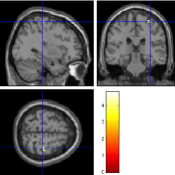

Once the reduced FOV images are available, the proposed pMRI 4D-UWR-SENSE algorithm and its early UWR-SENSE version have been utilized in a final step to reconstruct the full FOV EPI images and compared to the mSENSE Siemens solution. For the wavelet-based regularization, dyadic Symmlet orthonormal wavelet bases [48] associated with filters of length 8 have been used over resolution levels. The reconstructed EPI images then enter in our fMRI study in order to measure the impact of the reconstruction method choice on brain activity detection. Note also that the proposed reconstruction algorithm requires the estimation of the coil sensitivity maps (matrix in Eq. (2)). As proposed in [4], the latter were estimated by dividing the coil-specific images by the module of the Sum Of Squares (SOS) images, which are computed from the specific acquisition of the -space centre (24 lines) before the scans. The same sensitivity map estimation is then used for all the compared methods. Fig. 5 compares the two pMRI reconstruction algorithms to illustrate on axial, coronal and sagittal EPI slices how the mSENSE reconstruction artifacts have been removed using the 4D-UWR-SENSE approach. Reconstructed mSENSE images actually present large artifacts located both at the centre and boundaries of the brain in sensory and cognitive regions (temporal lobes, frontal and motor cortices, …). This results in SNR loss and thus may have a dramatic impact for activation detection in these brain regions. Note that these conclusions are reproducible across subjects although the artifacts may appear on different slices (see red circles in Fig. 5). One can also notice that some residual artifacts still exist in the reconstructed images with our pipeline especially for . Such strong artifacts are only attenuated and not fully removed because of the high level of information loss at .

| mSENSE | 4D-UWR-SENSE | ||

| Axial |  |

|

|

| Coronal | |||

| Sagittal | |||

| Axial |  |

|

|

| Coronal | |||

| Sagittal |